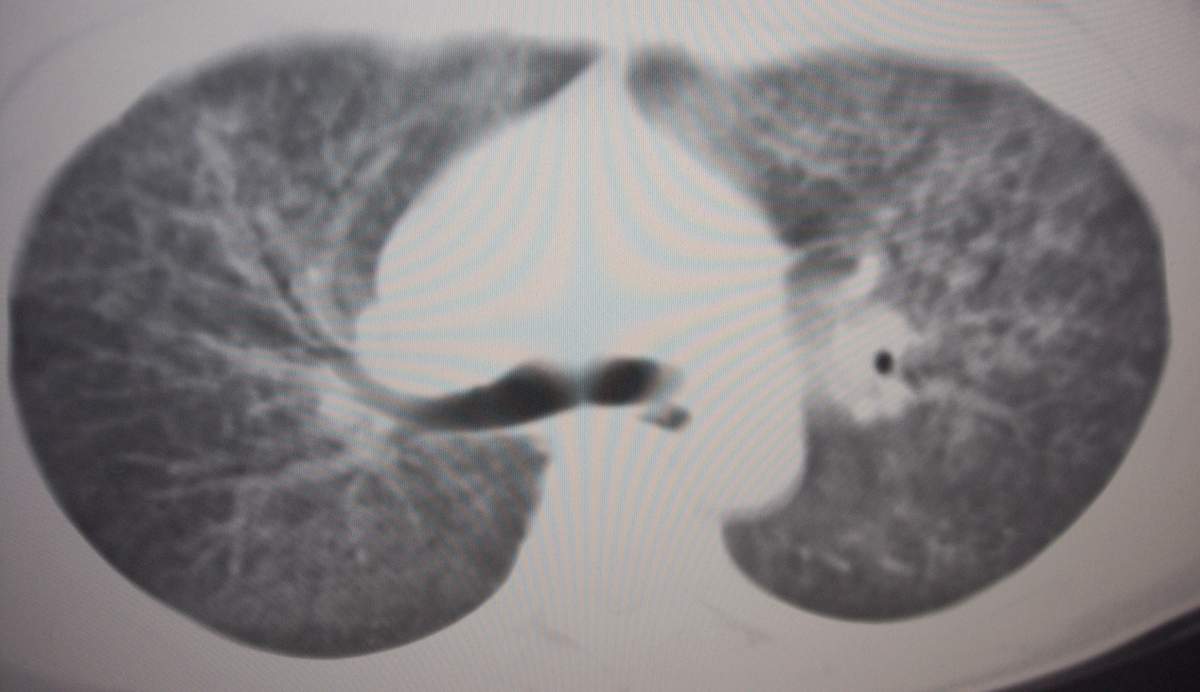

女,咳嗽、气喘2月余。

双肺纹理增多,紊乱,呈网格状,期间搀杂斑片及磨玻璃样阴影.考虑;感染性病变_首先考虑:特殊感染:嗜酸性肺病.

双肺弥漫磨玻璃样影,边界不清,似蝶翼征。肺纹理增多。

考虑:肺泡蛋白沉积症。建议临床进一步检查。